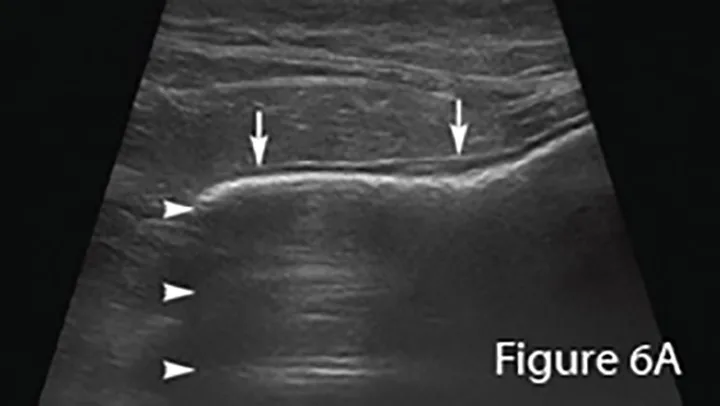

Ultrasound image of an enlarged intestine (arrows) showing large amount of reverberation artifact (arrowheads) caused by luminal gas. This prohibits visualization of the far wall of this loop of bowel. The ultrasound impression was a distended colon.

Lateral (Figure 6B) and ventrodorsal (Figure 6C) abdominal radiographs of severely distended segment of bowel identified sonographically and properly diagnosed as severe small intestinal obstruction (arrows). Of note, there is fecal-like material in the small intestine. An ileocecocolic mass was diagnosed during exploratory laparotomy. This mass was apparently obscured by gas during ultrasound examination. (C = colon)